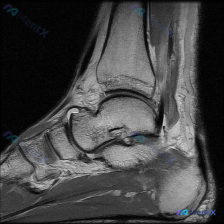

看到一个挺有参考价值的读片病例,整理了资料和分析思路分享给大家。 病例影像基础信息 这是一张放射影像-脚踝MRI-T1序列-矢状位图像: - 图像质量:信噪比尚可,解剖结构清晰,无明显运动伪影 - 解剖定位:踝关节近正中矢状位层面,可见胫骨远端、距骨、跟骨、舟骨及部分楔骨,后方跟腱、前方踝关节前隐窝...